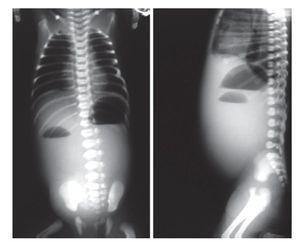

Se incluyeron 41 pacientes, 22 (55%) fueron del género masculino y 18 del género femenino (45%). Treinta y cinco (85%) eran originarios del Distrito Federal y 6 (15%) del Estado de México. El peso promedio al nacimiento fue 2,650 gramos y 24 fueron de término. La manifestación clínica constante fue vómito biliar, ya que se presentó en todos los pacientes. La imagen radiográfica de doble burbuja causada por la dilatación gástrica se observó en 31 pacientes (70.5%) (Imagen 1). La causa de la obstrucción duodenal fue atresia duodenal en 35 casos (86%) y páncreas anular en 6 (14%) (Foto 1). Todos tenían obstrucción posvateriana, 27 de la segunda porción del duodeno (66%) y 14 de la tercera (34%). Ocho (20%) tuvieron trisomía 21.

Imagen 1. Muestra la clásica imagen de "doble burbuja", producida por un nivel hidroaéreo en el estómago y otro en el duodeno. Traduce obstrucción duodenal como síndrome.

La obstrucción duodenal es causada por una gran diversidad de condiciones. Ladd las dividió en extrínsecas como la malrotación intestinal, la vena porta preduodenal y el páncreas anular; e intrínsecas como la atresia intestinal.5,6 La frecuencia de la obstrucción duodenal varía según la serie que se consulte, pero puede aparecer un caso por 10 a 20 mil recién nacidos vivos.7 La mortalidad antaño era superior al 50%,8 pero hoy día ha descendido hasta 6%, aunque se eleva al 70% cuando existe una disfunción anastomótica prolongada.9 La obstrucción congénita es mucho más común que aparezca en varones y distal al ámpula de Vater. La atresia es más frecuente que el páncreas anular o cualquier otra forma de obstrucción.10 En una delas series publicadas, el defecto se acompañó de condiciones asociadas destacando la combinación de defectos del duodeno,11 la trisomía 21, la atresia esofágica con fístula traqueoesofágica12 y anomalías vertebrales con menor frecuencia.13 En su presentación típica, la obstrucción del intestino delgado proximal se caracteriza por vómito biliar, dilatación gástrica y distensión del abdomen superior. El hallazgo radiológico casi siempre presente es el denominado por Gross como "imagen de la doble burbuja", la que se considera una indicación indiscutible de intervención quirúrgica.5